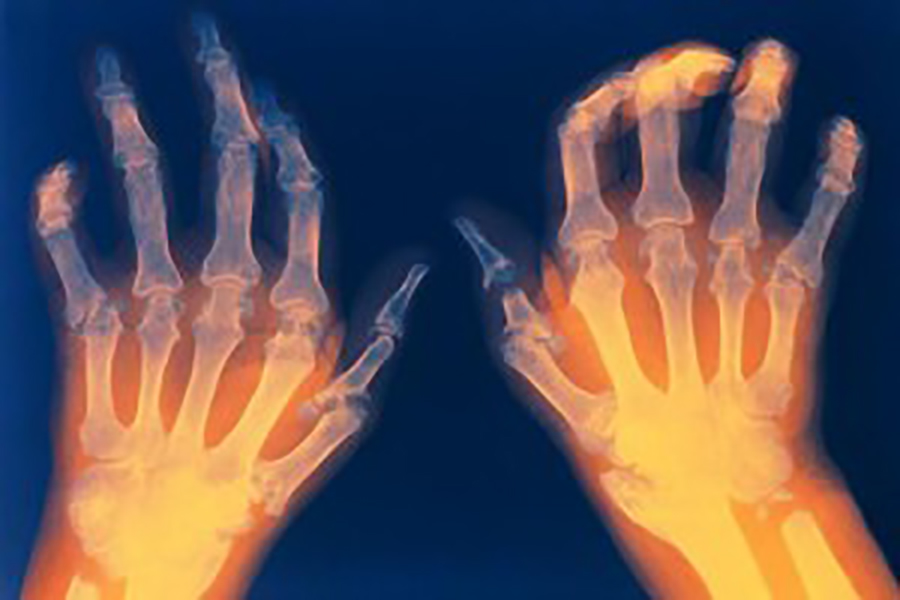

可能很多人都会有这样的经历,每当天气变化总感觉身体不舒服,或者是关节痛。尤其是曾经受过伤的朋友,愈发明显。中医把这个叫做风湿性关节痛。然而,有一种遇到寒冷或者天气变化感觉不舒服,甚至症状加剧的叫做风湿寒性关节痛!